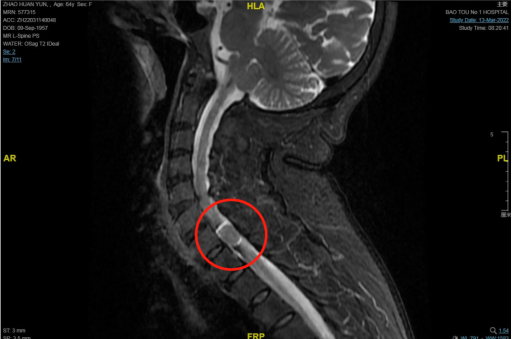

神经外科副主任赵志军接诊后,经MR检查,诊断为颈7-胸1椎管内占位,由于脊髓受到挤压,导致患者的下肢功能出现障碍。

神经外科主任张春阳教授通过影像学资料及患者症状明确诊断,考虑为椎管内脊膜瘤,建议进行手术治疗切除肿瘤。